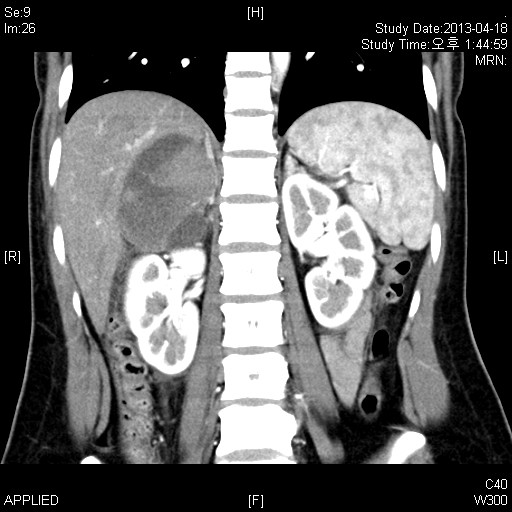

Context Adrenal cavernous hemangioma is a rare type of tumor that is usually diagnosed post-operatively. There have only been approximately 63 cases reported in the literature to date. Case report We report a case of adrenal cavernous hemangioma in a 27-year-old pregnant woman. The mass was discovered on ultrasonography when she visited a gastroenterologist for vague epigastric discomfort and vomiting. The laboratory tests were within normal limits and did not show any features suggestive of adrenal endocrinologic dysfunction. Computed Tomography (CT) revealed a well-defined 7.8 × 7.8 oval mass in the right adrenal gland with speckled calcifications. The mass was removed by transabdominal laparoscopic surgery. Strong positive immunostaining for CD31 and CD34 with weakly positive staining for podoplanin/D2-40 confirmed the diagnosis of cavernous hemangioma. Conclusions We reviewed 52 case reports of adrenal cavernous hemangioma in an attempt to identify tumor characteristics. More than half of the patients reviewed showed a heterogeneous internal structure of the mass with peripheral patchy enhancement on CT. They also showed focal or speckled calcifications either on X-ray or CT. Nevertheless, many of these characteristics overlap with the imaging phenotypes of other common diseases of the adrenal gland and therefore do not seem to provide definite evidence for differential diagnosis. Laparoscopic approach is a feasible and safe modality to remove adrenal cavernous hemangiomas because they seem to form a rigid fibrotic capsule; hence the risk of bleeding due to surgical manipulation is relatively low.